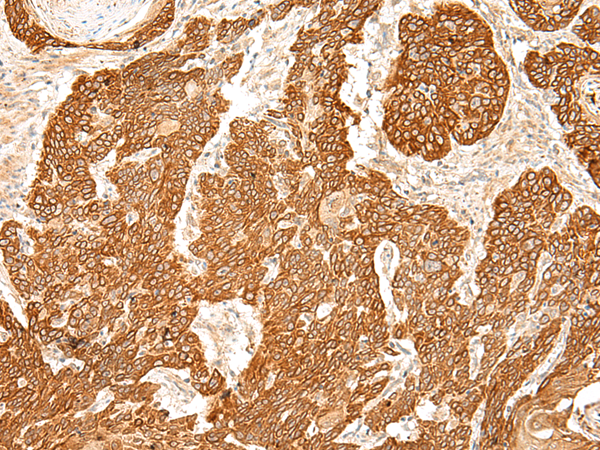

分类: 科研抗体货号: P13474别名: MEA-2; GCP170应用: WB,IHC反应种属: Human